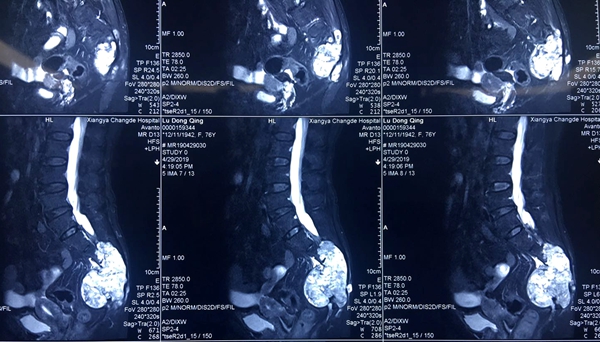

家人带卢奶奶到当地医院求诊,诊断为“痔疮”,经过一段时间治疗后效果不佳。疼痛在进一步加剧,剧痛难忍的她在外甥的推荐下来到湘雅常德医院骨科门诊,经CT 检查提示:骶椎占位性病变,以“骶椎肿物”收到骨科住院治疗。

入院后,经全面检查和肿块穿刺活检术后患者骶尾部脊索瘤诊断明确,手术是解除患者痛苦的最佳治疗方式。但由于肿块较大,且患者高龄,又因长期经受病痛折磨,身体耐受力差,手术风险高,为确保患者安全,张朝跃教授团队邀请了放射介入科、肿瘤科、普外科、泌尿外科、妇科、麻醉科、手术室、ICU相关学科专家,在3D打印的模型下直观的了解肿块与其周围血管、神经、组织的解剖结构,共同进行了疑难病例讨论,针对患者术中可能出现的紧急情况制定了详细的应急预案。为减少术中出血,确保患者安全,肿块切除术前由放射介入科团队为患者进行髂内动脉栓塞术。